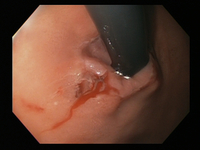

Um clipe do tipo "through-the-scope" instalado no centro da lesão (sem infusão prévia de adrenalina, neste caso)

Do acervo de Juan Carlos Munoz, MD, University of Florida